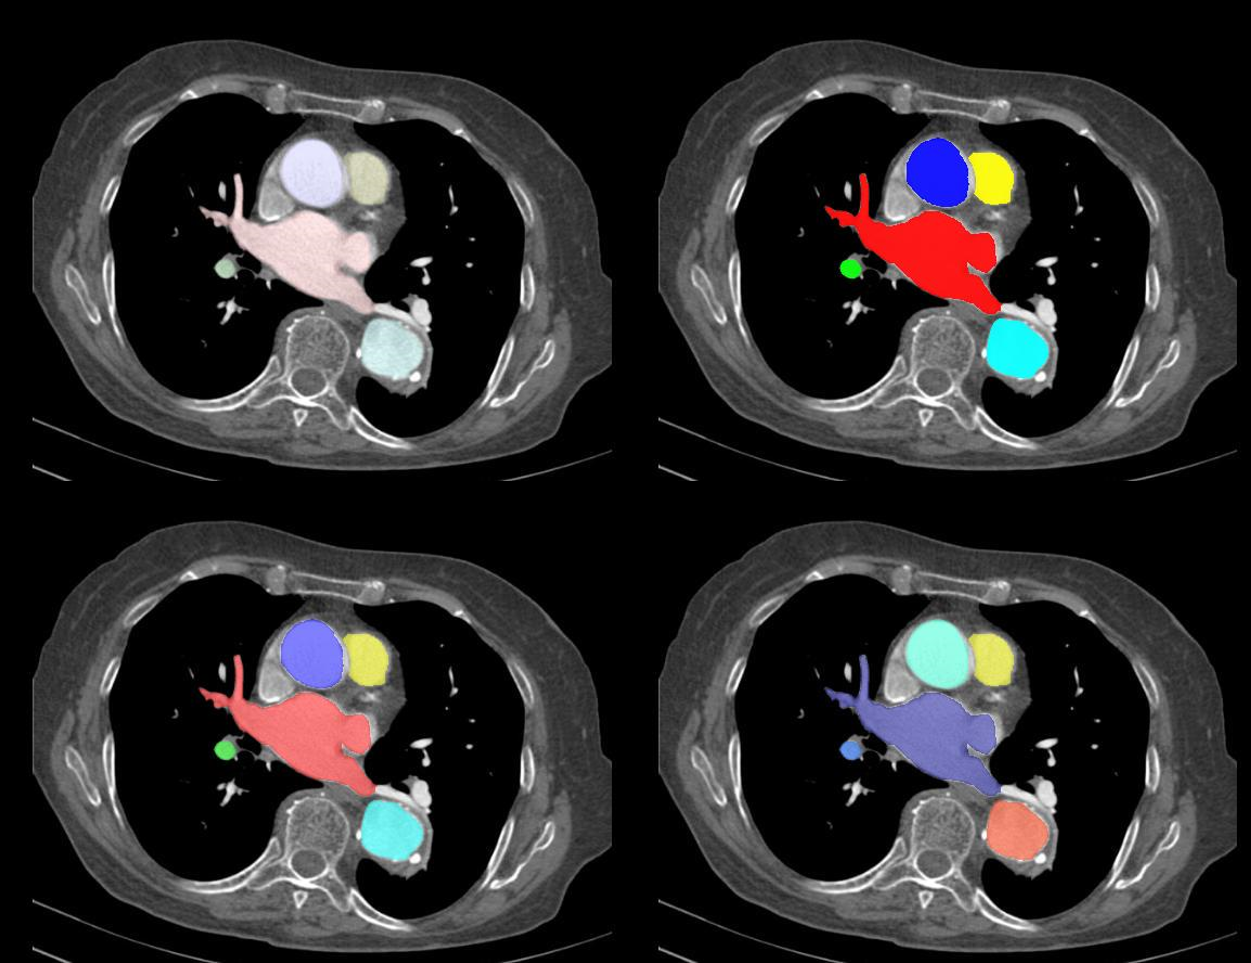

测试

% 自己调色,美滋滋

color1 = [1,0,0; 0,1,0; 0,0,1; 1,1,0; 0,1,1];

alpha1 = 0.1;

colorimg1 = drawlabel2image(im,label,color1,alpha1);color2 = [1,0,0; 0,1,0; 0,0,1; 1,1,0; 0,1,1];

alpha2 = 0.9;

colorimg2 = drawlabel2image(im,label,color2,alpha2);color3 = [1,0,0; 0,1,0; 0,0,1; 1,1,0; 0,1,1];

alpha3 = 0.5;

colorimg3 = drawlabel2image(im,label,color3,alpha3);% 不想配色,直接用MATLAB自带的colormap

color4 = jet; % matlab自带

alpha4 = 0.5;

colorimg4 = drawlabel2image(im,label,color4,alpha4);% 显示

figure

subplot(2,2,1), imshow(colorimg1)

subplot(2,2,2), imshow(colorimg2)

subplot(2,2,3), imshow(colorimg3)

subplot(2,2,4), imshow(colorimg4)

结果如下

在这里插入图片描述